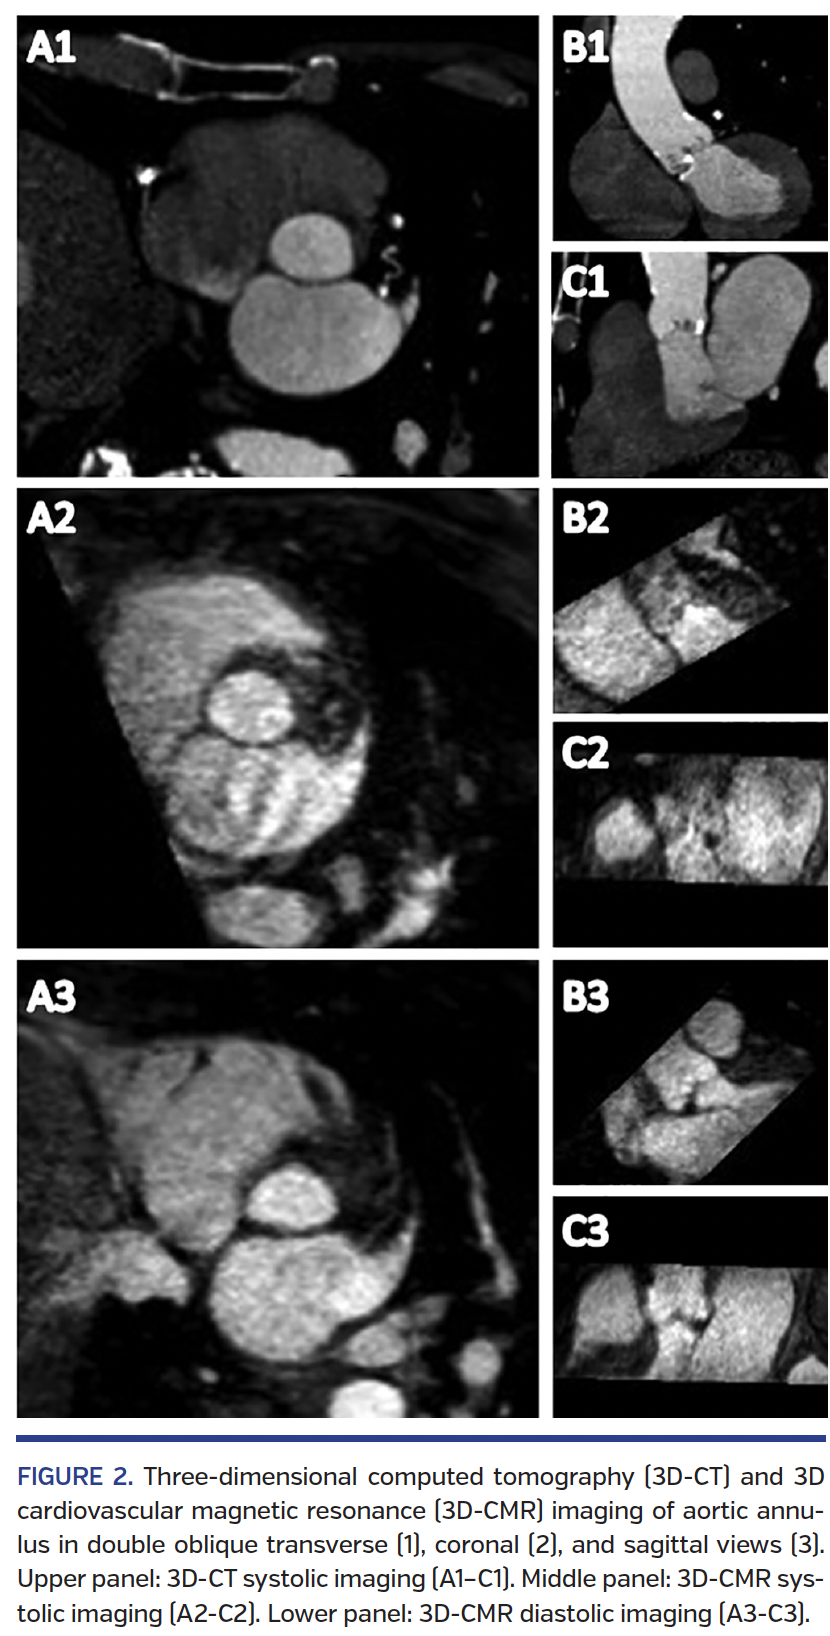

3D-CMR and CT measurements. Aortic annulus dimensions assessed by 3D-CMR and CT are shown in Table 2 and Figure 2. We acquired 3D-CMR and CT image in systole successfully with sufficient image quality in all patients. For diastolic 3D-CMR, 4 patients (19%) were excluded due to poor quality as a result of navigator failure in the setting of pleural effusion (n = 1), ECG-gating failure in atrial fibrillation (n = 2), and incomplete diastolic plane (n = 1). Three cases of 2D-CMR (14%) were excluded due to the lack of an acquired imaging slice at the exact location of the aortic annulus.

Image reconstruction and analysis of the aortic root. We performed all image analyses on separate computer workstations using the same software (Aquarius iNtuition; TeraRecon). We maneuvered coronal and sagittal oblique views to define the orientation on the aortic valve. The corresponding double-oblique transverse view was adjusted to transect through the most caudal attachments of all three native cusps, the virtual ring was reconstructed using CT as well as 3D-CMR data sets. Furthermore, we evaluated the distances between the annulus and the ostium of the left coronary artery as well as the right coronary in the coronal view using CMR and CT.

We measured the annulus at the lowest hinge point of the leaflets at the virtual basal plane during systolic phase reconstructions from 20%-45% of the R-R interval by CT. Both systolic phase and diastolic phase reconstructions were measured using 3D-CMR and 2D-CMR. We measured maximum and minimum diameters, cross-sectional area (CSA), perimeters, and area-derived average diameter by manually tracking the luminal contours on double-oblique transverse planes. We measured the distance from the aortic annulus to left main ostium and right coronary artery ostium in systole by CT and 3D-CMR.